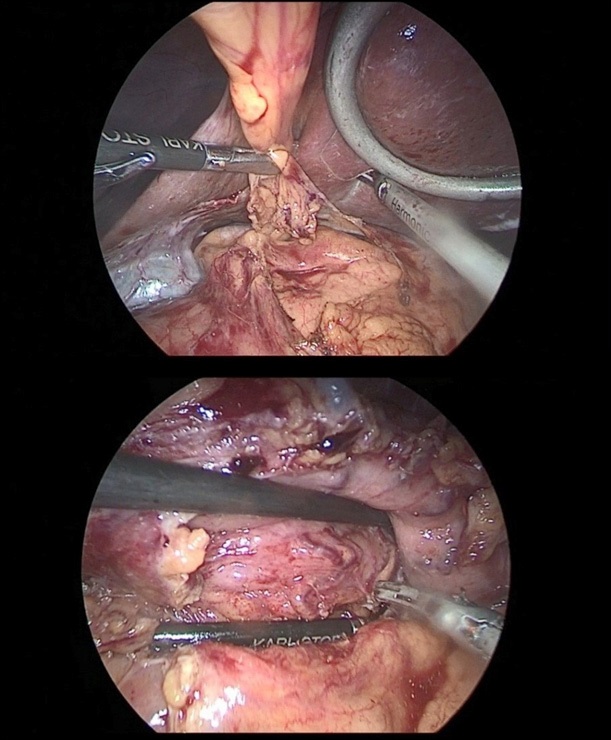

The stomach is mobilized to pyloric sphincter. Next, was performed mobilization along the lesser curvature of the stomach (Figure 8). For this, the lesser omentum was resected, lymph node dissection of I, III, V, VII groups of lymph nodes. The left gastric artery was clipped (Figure 6a,b) and transected (Figure 7).

Figure 6a,b: Resection of the lesser omentum with removed I, III, V, VII group of lymph nodes.

Figure 7: The left gastric artery was clipped with a Hemo-Lock (X) clip, with additional fixation with tantalum clips.